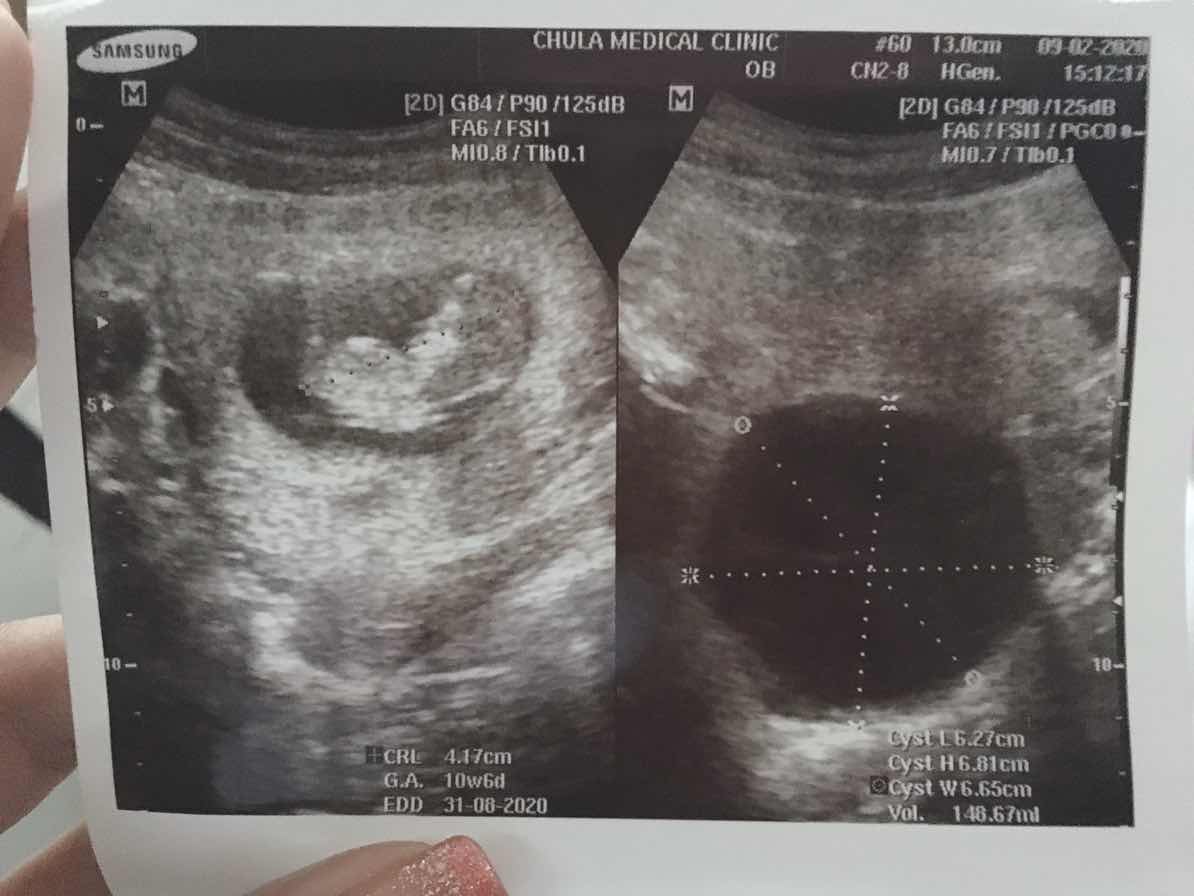

10w ค่ะ